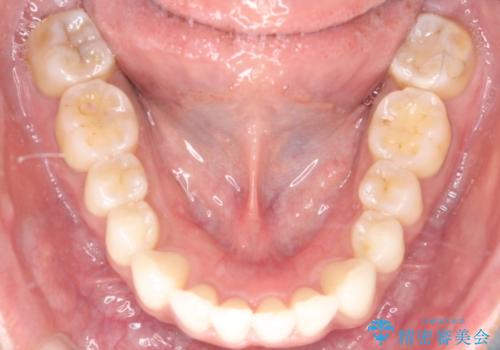

1年半の治療期間を経て、重なり合っていた前歯はスムーズに整列し、理想的なアーチ状の歯並びへと改善されました。抜歯を行わずに治療を完了したことで、噛み合わせのバランスを維持しながら、審美性を大きく向上させることができました。現在は保定期間に入り、美しい状態を維持されています。

- 矯正治療後の保定が不十分だと後戻り(元の位置に戻ろうとする動き)をします